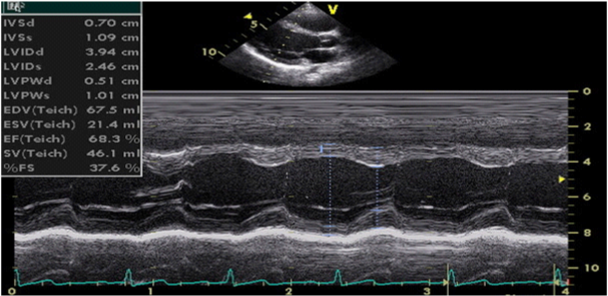

1. Teichholz method–calculation of LV volumes and EF is done by measuring the LV linear dimensions in systole and diastole (parasternal long axis, at the level of the mitral chords), measuring the interventricular septum thickness (IVS) and the posterior wall thickness (PW) (Figure 1)

Figure 1 M-mode echocardiography (parasternal long-axis view, calculation of LV volumes and ejection fraction by Teichholz method).